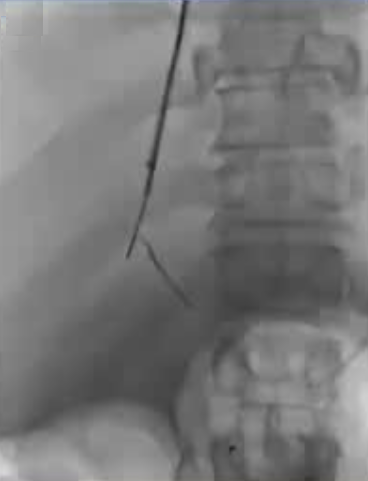

在进行门静脉血栓治疗时施行经皮穿刺取栓术所增加的额外风险主要是由于创伤所致。 从技术层面来看,要穿刺进入血栓形成的血管是相当困难的,而且有可能会反复出现成功与失败的情况。 降低风险的方法包括对静脉瓣进行成像,或者安装一个装置来引导穿刺操作。

通过经皮经脾路径具有显著优势,能够使用 4Fr 细导管和导丝进行逆向再通操作,以 10 毫米的圈套器作为经颈静脉穿刺目标,通过Avitene 完成经颈静脉门静脉穿刺。